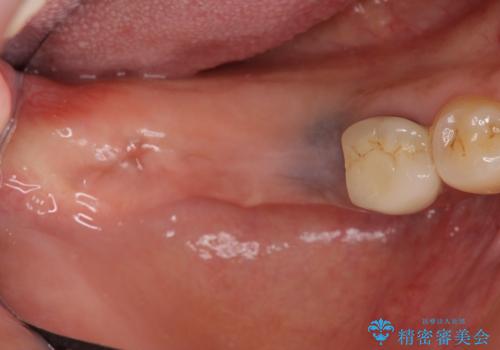

- 失った右下奥歯の機能回復を求めて来院されました。

取り外しの必要な入れ歯、もしくは手術の必要なインプラントのご提案を行い、しっかりと奥歯で物を噛みたいとの要望からインプラント治療を計画します。

インプラントの埋入には十分な骨量が必要ですが、虫食い状に骨が足りなかった為インプラントの埋入と同時に骨の増成を行いました。